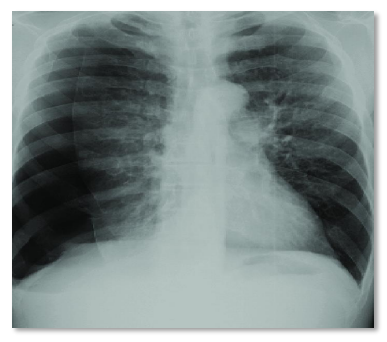

Paciente vítima de politrauma entre carro e moto, no local se levantou, consciente. Após alguns minutos, iniciou quadro de dor torácica, desconforto respiratório, elevação de hemitórax direito, com elevação de cúpula e distensão de veias do pescoço, ipsilateral.